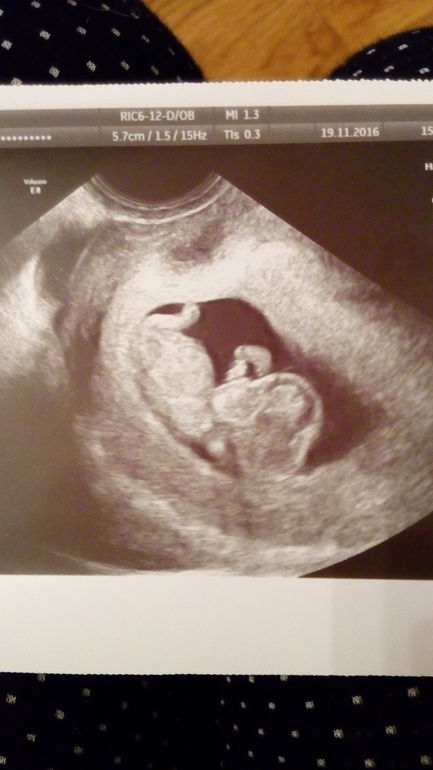

Вот он, наш карапузик на сроке 10 недель))))

Не ожидала, что он уже такой человечек) Сердцебиение 152, ктр 3.1см, пя 3.8 см.